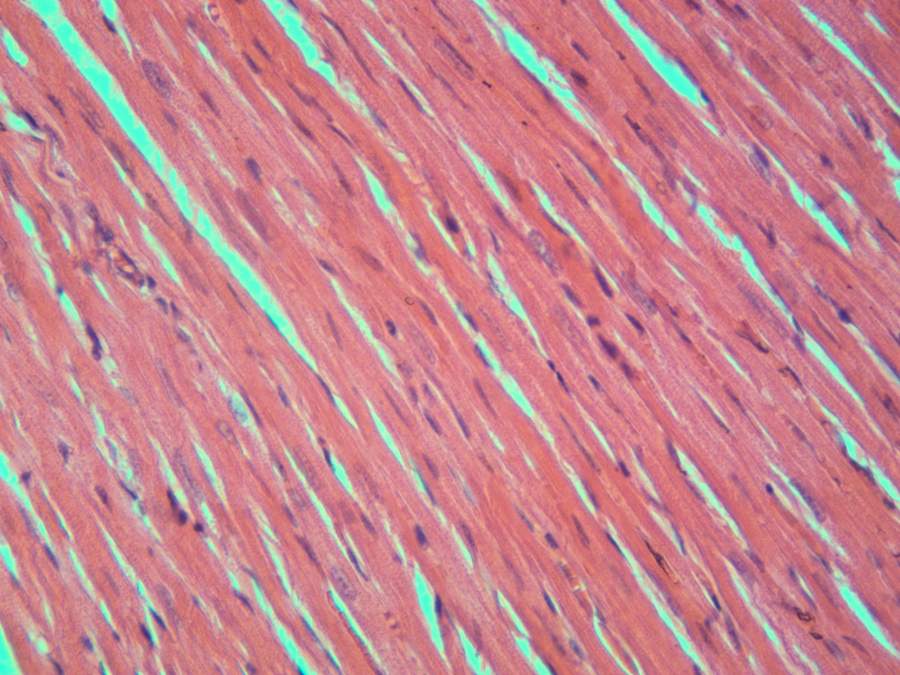

急求!光学显微镜放大倍数! 已有1人参与